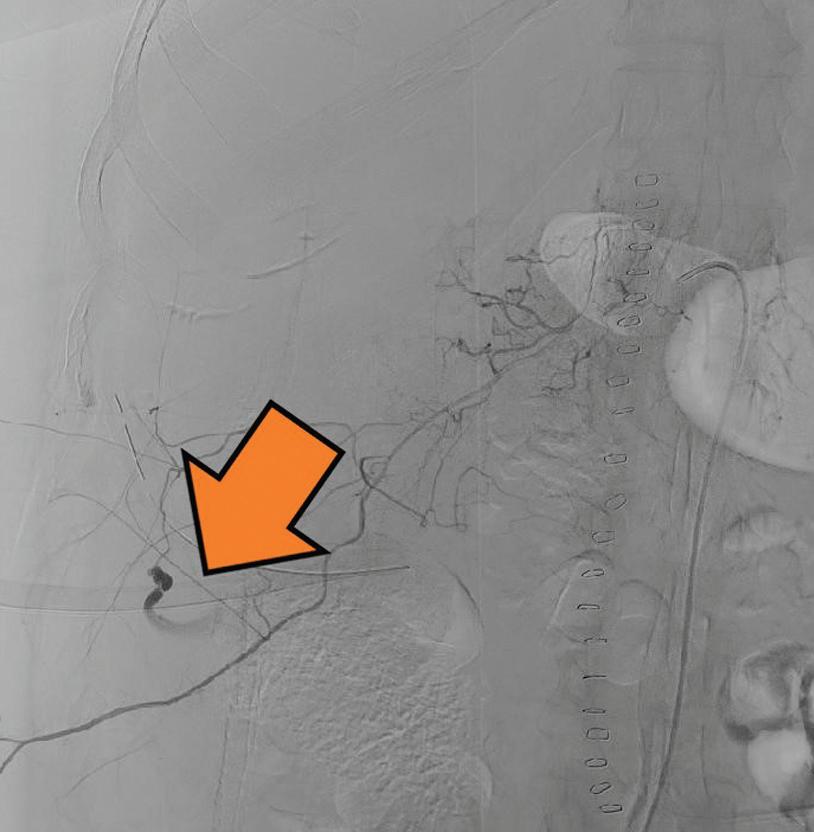

Vazografická obliterace krvácející arterie zádových svalů po bilaterální nefrektomii

Vasographic obliteration of a bleeding back muscle artery after bilateral nephrectomy of polycystic kidneys

Václav Krejčí, Miloš Broďák, Antonín Krajina, Jaroslav Pacovský